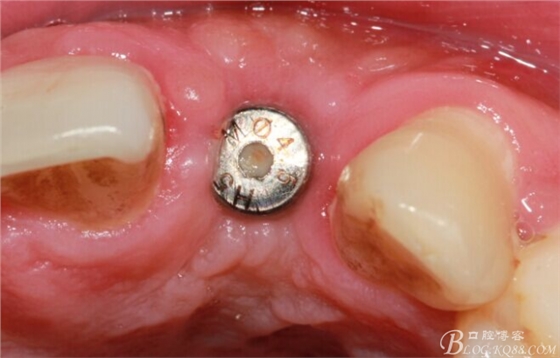

4個(gè)月后,唇側(cè)豐滿度尚可,與鄰牙之間齦乳頭完整。

保留齦乳頭翻小瓣。

翻開后驚喜的發(fā)現(xiàn),術(shù)區(qū)成骨非常好,去除部分骨才暴露那顆長(zhǎng)鈦釘。